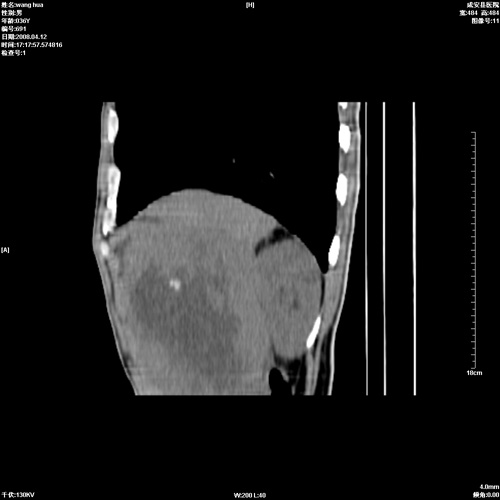

标题: CT12809:男36岁,自感上腹胀5天,B超诊断为脾肾之间占位,血 [打印本页]

标题: CT12809:男36岁,自感上腹胀5天,B超诊断为脾肾之间占位,血

请各位老师先分析一下定位 明天做增强

脾脏明显增大,其内见巨大低密度灶,境界不清,病史较短,考虑恶性病变脾血管内皮细胞肉瘤可能。建议增强扫描与脾脏淋巴瘤及血管瘤鉴别。